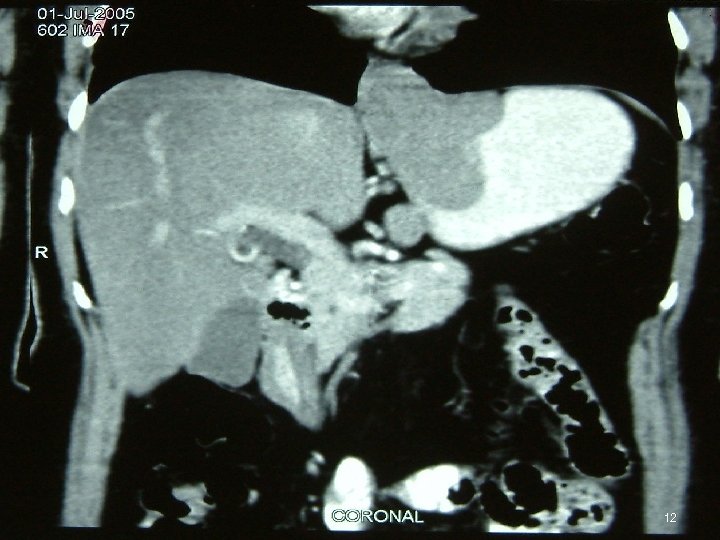

Investigations • • • Chest X Ray USG CECT EUS Ba Swallow 3

Diagnosis • FDG PET = mandatory ►FDG-PET CT scan is ideal • MD-CE-CT = image modality of choice for abdomen (if FDG-PET-CT is not available) • MR • Evaluate by Chol or RECIST criterion 46